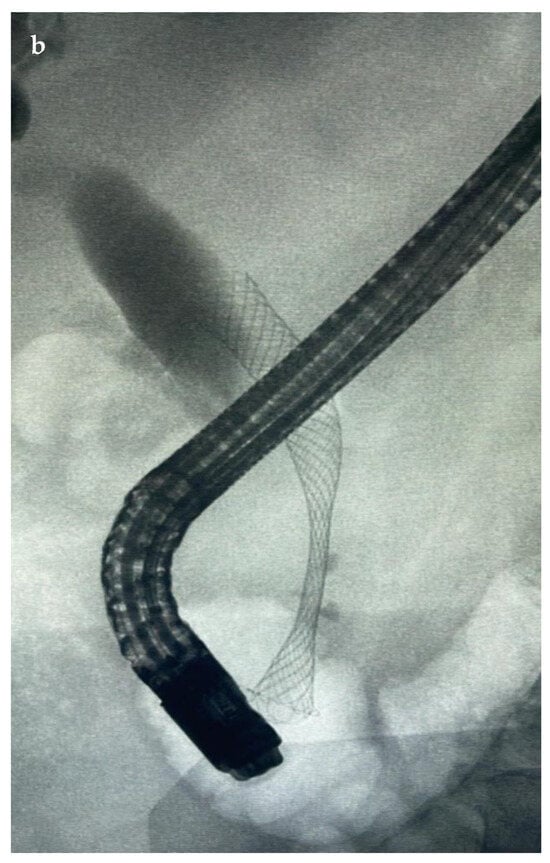

7.1.1. Endoscopic Biliary Stenting (EBS)

7.1.3. EUS-Guided Biliary Drainage (EUS-BD)

- Kawashima, H.; Ohno, E.; Ishikawa, T.; Mizutani, Y.; Iida, T.; Yamamura, T.; Kakushima, N.; Furukawa, K.; Nakamura, M. Endoscopic management of perihilar cholangiocarcinoma. Dig. Endosc. 2022, 34, 1147–1156. [Google Scholar] [CrossRef]